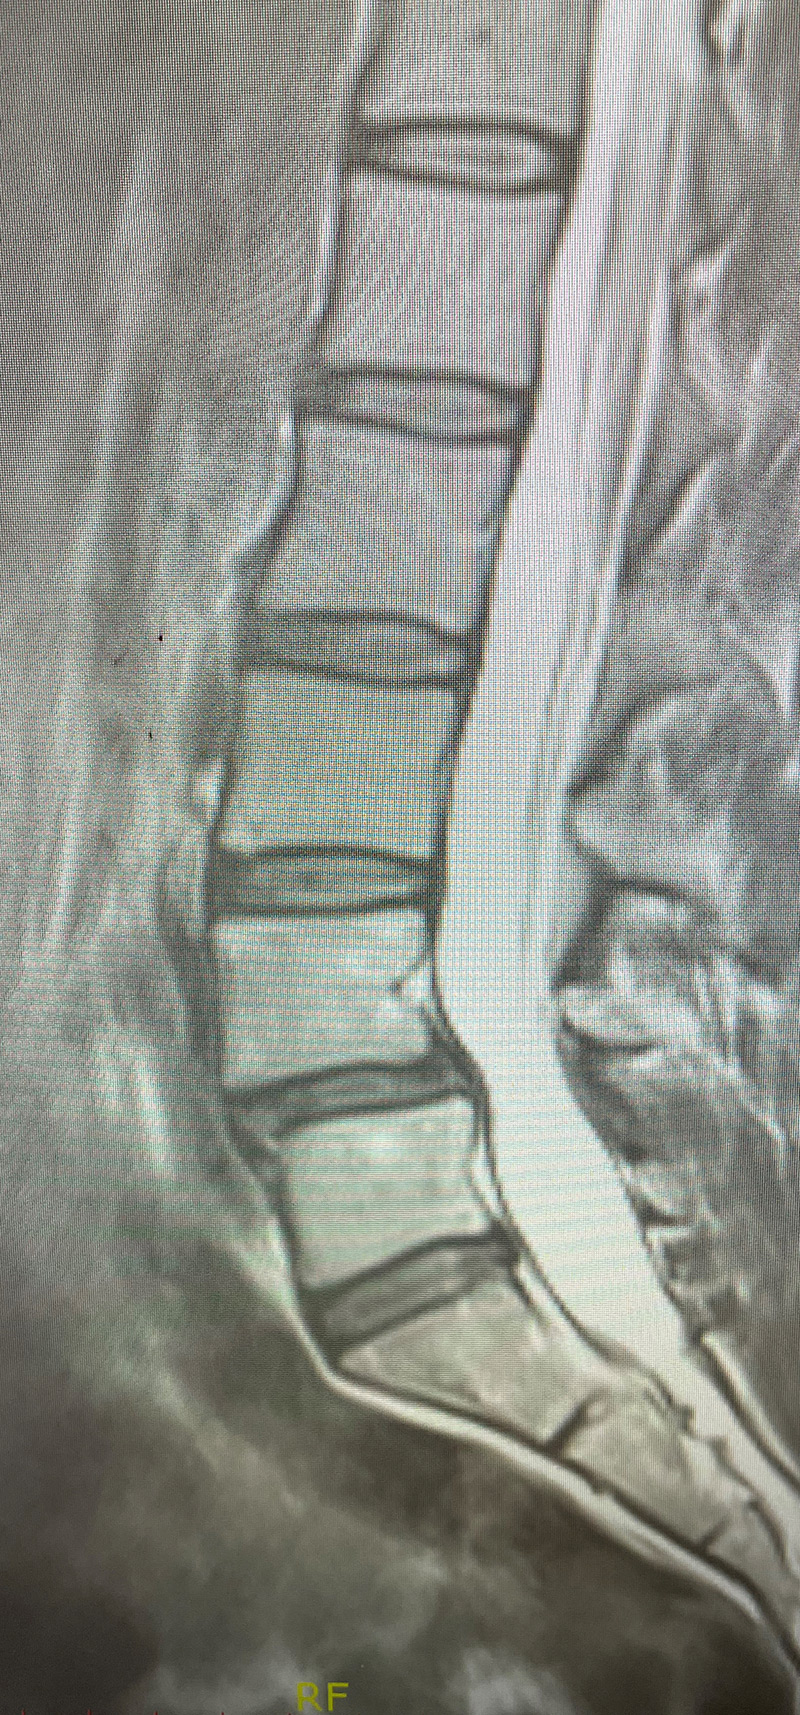

Figure 2

As a result, the patient has developed severe degenerative disc disease with collapse and a retrolisthesis above. There is also a left sided disc osteophyte complex that is causing foraminal stenosis and mild thecal sac compression. Up to this point, the patient had failed all means of conservative management including physical therapy, epidural injections, and medicine. Because of the current worsening of left leg pain another MRI was performed which demonstrated a significant increase in the disc herniation with severe thecal sac compression and nerve root compression (Fig 2). It was decided to schedule the patient for decompression, discectomy, and fusion because of the progression of disc herniation and retrolisthesis.